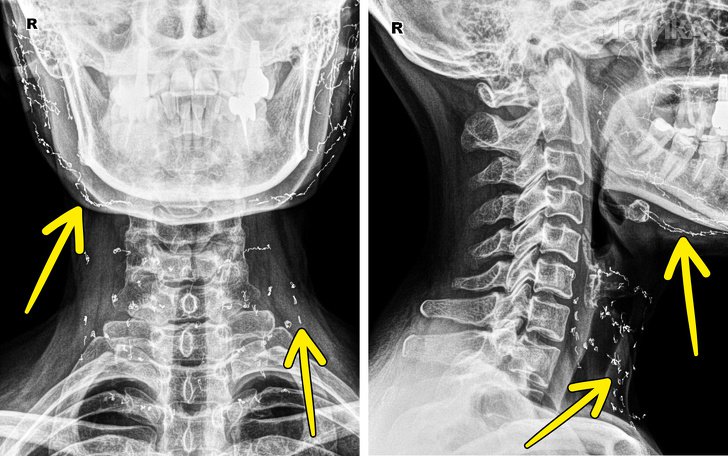

8. Снимка на пациент кој бил подложен на затегнување со златни нишки